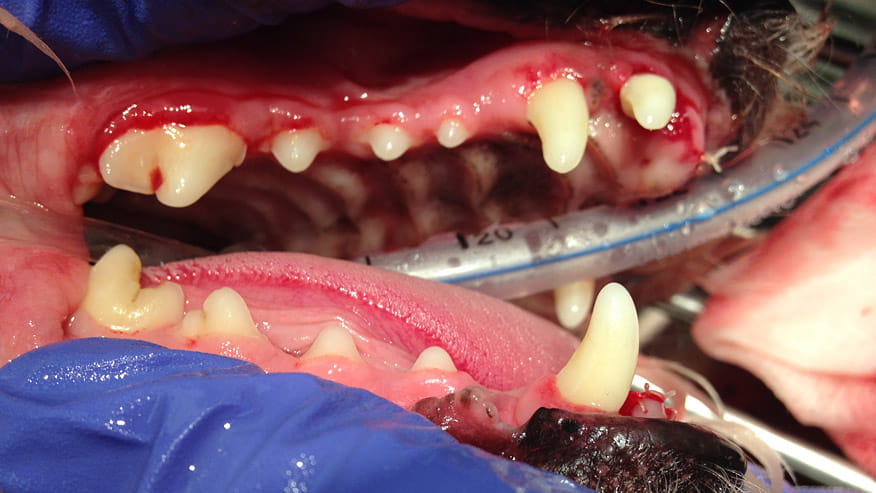

• VCA Wakefield Animal Hospital Dental Care

Dogs and cats don't often get cavities. But they do frequently suffer from other types of dental disease. Periodontal or gum disease, in fact, is the number one illness found in both dogs and cats.... Read more

Our hospital offers a variety of Dentistry Services. At your pet's yearly examination it may be determined that they require a dental cleaning. Routine veterinary dentistry involves prophylaxis (teeth cleaning), polishing and a full oral examination.... Read more